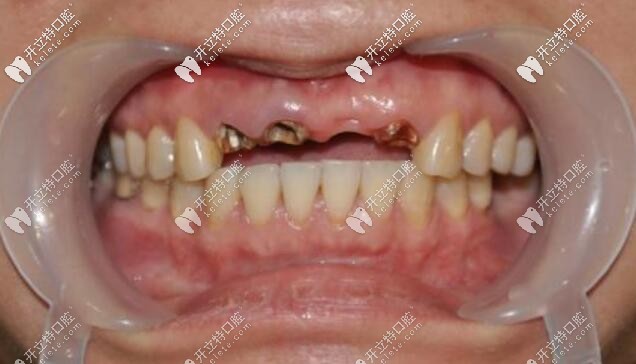

牙齦出血牙周炎怎么治療牙齒缺失發(fā)布時(shí)間: 2025-04-21

當(dāng)牙齦出血時(shí),大部分人都會(huì)不在意,但是一定要警惕是否是牙周炎在作祟!這不年僅30多歲的他因牙齦突然無故出血未在意,導(dǎo)致一口牙都無法保留,只能拔掉做假牙~